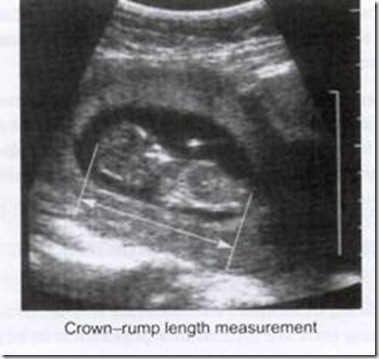

Pengukuran CRL – Crown Rumph Length adalah langkah penting pencitraan pada kehamilan kurang 12 minggu

Setelah itu, pengukuran BPD – Biparietal Diameter dan pengukuran tulang panjang seperti os.femur - Femur Length ( FL ) dapat digunakan untuk menentukan usia kehamilan sebelum trimetser III kehamilan.